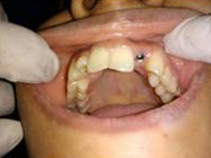

Single Tooth Implant

Pre Operation